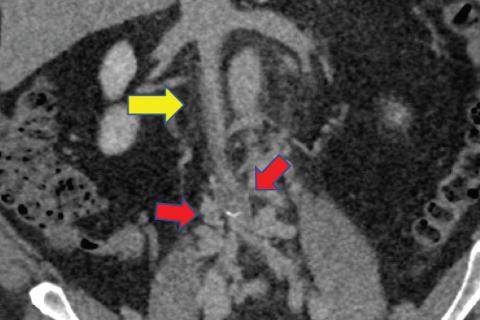

Deep vein thrombosis is the development of thrombus in the deep venous system, typically in the legs. Conventional first-line therapy is management with oral anticoagulants or occasionally parenteral... Read More